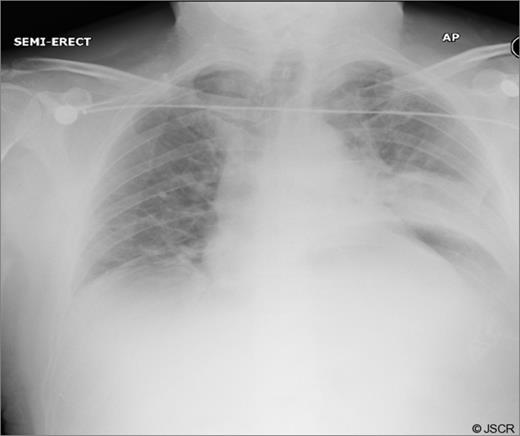

Chest pain persisted and the patient required higher pressure CPAP to maintain adequate oxygenation. Auscultation consistently showed decreased air-entry in the lung bases. On day 3, a repeat chest x-ray showed a left lower lobe collapse above the gastric bubble in the mid zone of the chest (Fig. 4 & 5). CTPA done on the same day to exclude pulmonary embolism confirmed a para-oesophageal hernia that was pushing against the left lung base. Ultrasound scan of the left chest also showed movement of the diaphragm below the gastric bubble.

Post-op CT-scan demonstrating the left sided pleural effusion with collapse /consolidation & patchy opacification on the right side.